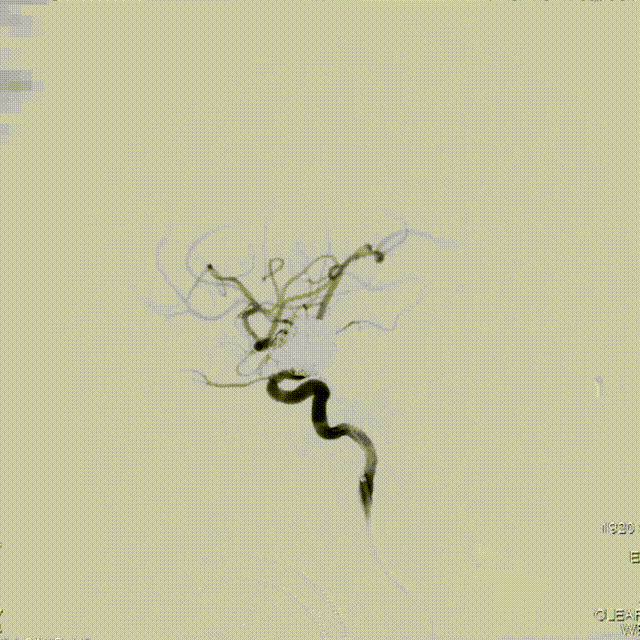

术后检查

术后即刻正侧位造影,动脉瘤滞留明显、远端血流通畅。

正位造影

侧位造影